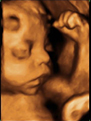

Ecografía 4D del tercer trimestre: Bebé abriendo la boca

Ecografía 4D de feto abriendo la boca en el tercer trimestre de embarazo

El bebé ha crecido mucho y la ecografía puede detallar partes de su cuerpo, como en ésta que vemos: con las manos cerca de la cara, en la postura fetal característica, el niño mueve ligeramente las extremidades y abre la boca. Se puede apreciar perfectamente la fisonomía de la criatura.